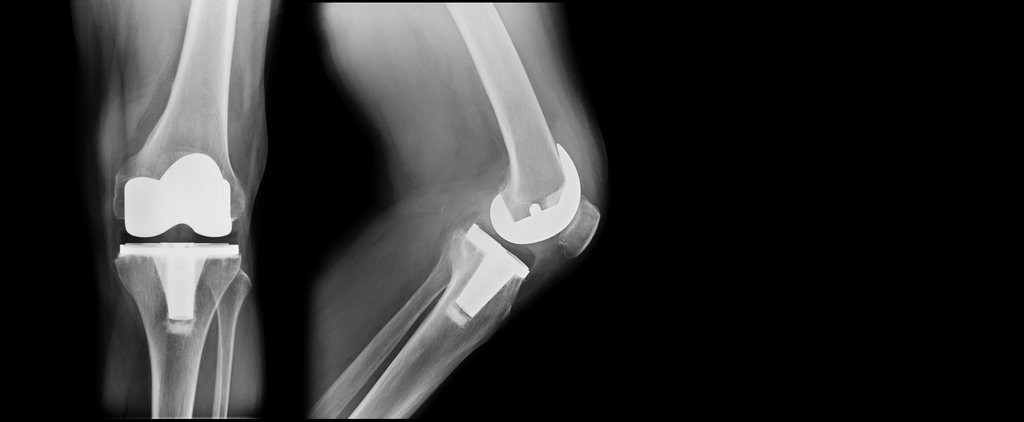

Total Knee Replacement: What to Expect Before, During, and After Surgery

Total knee replacement surgery typically takes one to two hours and involves removing damaged cartilage and bone from the thigh bone, shin bone, and kneecap. The surgeon then replaces these surfaces with artificial components made from metal alloys and high-grade plastics designed to replicate normal knee function and provide decades of reliable service.

Modern surgical techniques often utilize computer-assisted navigation or robotic systems to ensure precise implant positioning and optimal alignment. These advanced technologies help surgeons achieve more accurate bone cuts and implant placement, potentially leading to better long-term outcomes and improved joint function. The artificial joint components are secured using either bone cement or are designed to allow your natural bone to grow into the implant surface.